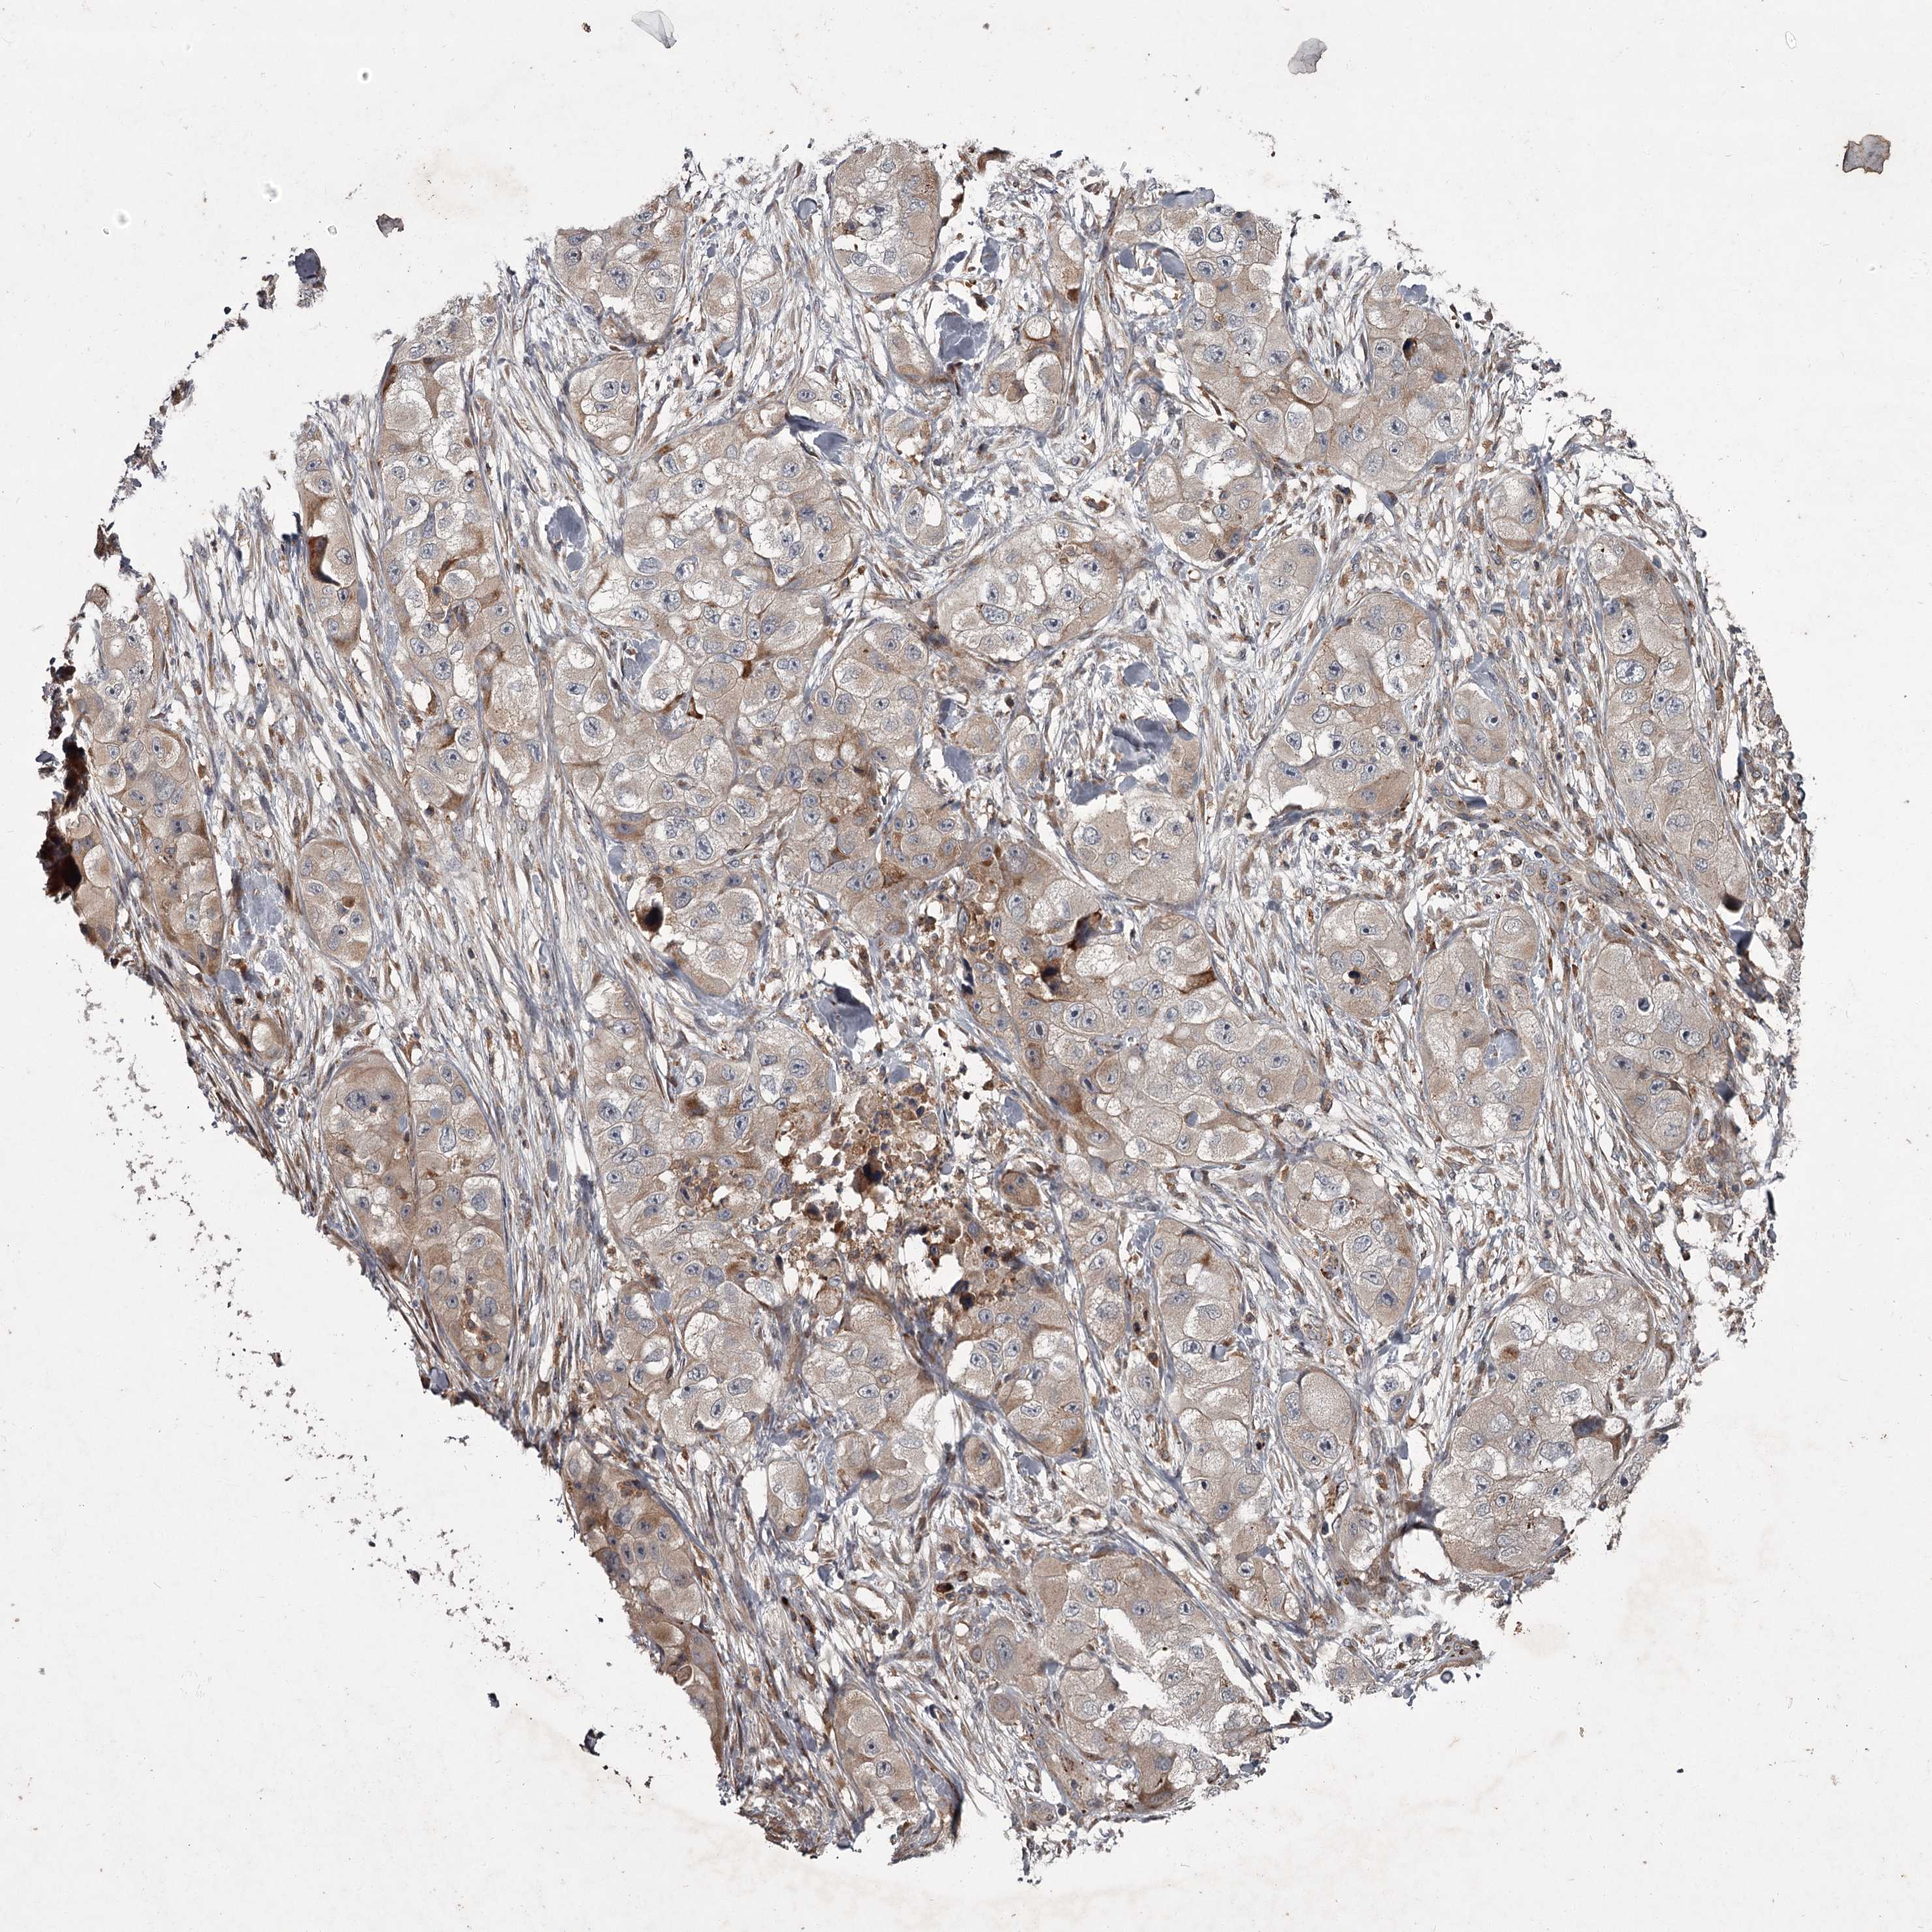

SKIN CANCER - Protein expressioni

A mouse-over function shows sample information and annotation data. Click on an image to view it in a full screen mode. Samples can be filtered based on level of antibody staining by selecting one or several of the following categories: high, medium, low and not detected. The assay and annotation is described here.

Antibody staining in the annotated cell types in the current human tissue is reported as not detected, low, medium, or high, based on conventional immunohistochemistry profiling in selected tissues. This score is based on the combination of the staining intensity and fraction of stained cells.

Each image is clickable and will lead to virtual microscopy that enables deeper exploration of all samples and also displays staining intensity scores, fraction scores and subcellular localization as well as patient and tissue information for each sample.

Antibody HPA038717

Basal cell carcinoma